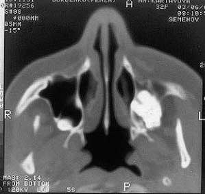

Получение компьютерной томограммы (среза) на выбранном уровне основывается на выполнении следующих операций: 1) формирование требуемой ширины рентгеновского луча (коллимирование); 2) сканирование пучком рентгеновского излучения, осуществляемого движением (вращательным и поступательным) вокруг неподвижного объекта устройства «излучатель – детекторы»; 3) измерение излучения и определение его ослабления с последующим преобразованием результатов в цифровую форму; 4) машинный (компьютерный) синтез томограммы по совокупности данных измерения, относящихся к выбранному слою; 5) построение изображения исследуемого слоя на экране видеомонитора (дисплея). Пример рентгеновской компьютерной томограммы на рис. 9.

Рисунок 7 – Компьютерная томография верхнечелюстных пазух. Сверхкомплектный зуб в левой гайморовой пазухе.